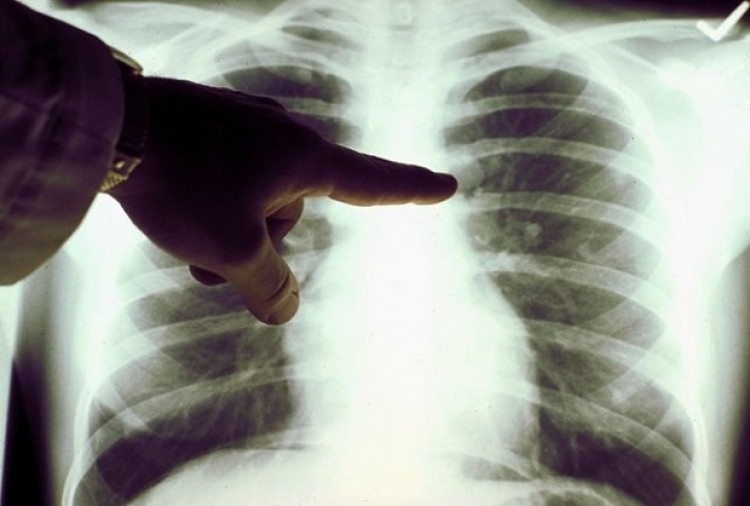

Si bien el tabaquismo constituye el principal factor de riesgo para desarrollar la enfermedad, existe un grupo de pacientes -entre el 10 y el 15 por ciento de los casos- que lo desarrollan por alguna alteración a nivel molecular, y muchas veces no son fumadores.Especialistas en oncología destacaron que aunque el cáncer de pulmón no suele manifestarse durante las fases iniciales de la enfermedad, es recomendable estar atentos a una serie de síntomas que si bien individualmente podrían corresponder a muchas otras afecciones, en su conjunto representan un signo de alerta para al menos concurrir a la consulta médica y así descartar la enfermedad o, caso contrario, abordarla lo más tempranamente posible.Entre los principales síntomas se destacan la tos persistente, dolor constante en el pecho al respirar o toser, esputos con sangre, dificultades para respirar, sensación de falta de aire, infecciones frecuentes en los pulmones, ‘pitidos’ o ruidos al respirar, ronquera o cambios en la voz, sensación de que la comida se queda detenida en el tórax, bultos o masas en el cuello o en la clavícula, fatiga, pérdida del apetito y de peso, y dolor de huesos.El cáncer no es una sola enfermedad, sino un grupo de enfermedades que lo que tienen en común es el crecimiento anormal y desordenado de las células, que acaban formando unas masas denominadas tumores. Particularmente, el cáncer de pulmón provoca más muertes que el de colon, mama y próstata juntos, y en el mundo se diagnostican 1.600.000 nuevos casos cada año. En la Argentina es el tipo de cáncer que ocupa el primer lugar en mortalidad, con una cifra estimada de aproximadamente 9.000 defunciones por año.Respecto de los factores de riesgo para desarrollar la enfermedad, si bien el tabaquismo constituye el principal y la recomendación unánime es no comenzar a fumar y, si es fumador dejar de hacerlo o por lo menos no hacerlo delante de otras personas, existe un grupo de pacientes -entre el 10 y el 15 por ciento de los casos- que desarrolla cáncer de pulmón por alguna alteración molecular, independientemente de ser o no fumadores; esto incluye hombres y mujeres de todas las edades, inclusive jóvenes de 15 años de edad.En ellos, el tipo de cáncer que se presenta dependerá del gen que se altera y, para su tratamiento, hoy se cuenta con terapias ‘a medida’ para algunas de las alteraciones genéticas. Estas medicaciones son las denominadas ‘terapias dirigidas a blancos moleculares’ y tienen la particularidad de trabajar en distintas etapas de los procesos de proliferación de las células malignas, ofreciendo resultados muy alentadores.Para el del Dr. Claudio Martín, médico oncólogo, Jefe de Oncología Torácica del Instituto Alexander Fleming, “en la actualidad, las alternativas de tratamiento para un paciente con cáncer de pulmón se han ampliado enormemente y en muchos casos la posibilidad de cronificar la enfermedad es una realidad, gracias a la aparición de varias drogas nuevas que permiten su control”.El cambio en el tratamiento del cáncer de pulmón ha sido drástico en los últimos años: ahora se cuenta con muchas más herramientas que han permitido que los pacientes tengan una mejor calidad de vida y que la sobrevida se haya prolongado en forma significativa. Hace 10 años, no importaba el subtipo de tumor porque todos se trataban de la misma forma. En la actualidad, cada tipo de tumor de pulmón se aborda de manera diferente, en varios casos con medicaciones más específicas y con mejores resultados.La elección del tratamiento variará según el tipo y el estadio de la enfermedad. El Dr. Martín refiere que “si está localizada sólo en el pulmón, la cirugía es la elección. Si además compromete los ganglios que están en el mediastino (cavidad ubicada entre los pulmones), la opción será la radioterapia. Mientras que cuando nos enfrentamos a un cuadro con metástasis, es necesario estudiar si el tumor tiene algún cambio genético o molecular (mutación o rearreglo). Si no lo tiene, la indicación será la quimioterapia estándar, pero si presenta una mutación o rearreglo, es muy posible que podamos ofrecerle una terapia dirigida”. “Si bien se han descubierto muchas mutaciones en cáncer de pulmón, hay particularmente dos -la mutación EGFR y el rearreglo de ALK- para las cuales existen medicamentos aprobados y que son de primera elección. Es necesario evaluar la presencia de estas mutaciones en todos aquellos pacientes con el subtipo más frecuente de cáncer de pulmón (adenocarcinoma) y en aquellos tumores que ya se han diseminado a otros órganos”, agregó el Dr. Claudio Martín, quien también es oncólogo del Hospital María Ferrer. Acerca de la alteración ALK+Algunos subtipos de un cáncer de pulmón denominado ‘cáncer pulmonar de células no pequeñas’ (CPCNP)[6], que se estima representa entre el 85 y el 90% de los cánceres de pulmón, presentan cambios moleculares y son los que muchas veces se manifiestan en personas exfumadoras o que nunca fumaron. Uno de esos subtipos se origina porque diferentes porciones de dos genes (el EML4 y el ALK) se ven alteradas, creando la proteína de fusión ALK que promueve el desarrollo y crecimiento del tumor[7]. Hoy es posible mediante estudios de marcadores tumorales reconocer la alteración molecular e identificar a este CPCNP ALK+, un tipo específico que afecta a cerca de 72.000 personas en el mundo[8].A partir de allí, se puede orientar el tratamiento con terapias dirigidas especialmente a inhibir la alteración causante de este crecimiento tumoral, las que nos ofrecen la posibilidad de poder disminuir el tamaño y extensión de la enfermedad, prolongar la sobrevida del paciente libre de progresión, ofrecerle una mejor calidad de vida y disminuir los síntomas.